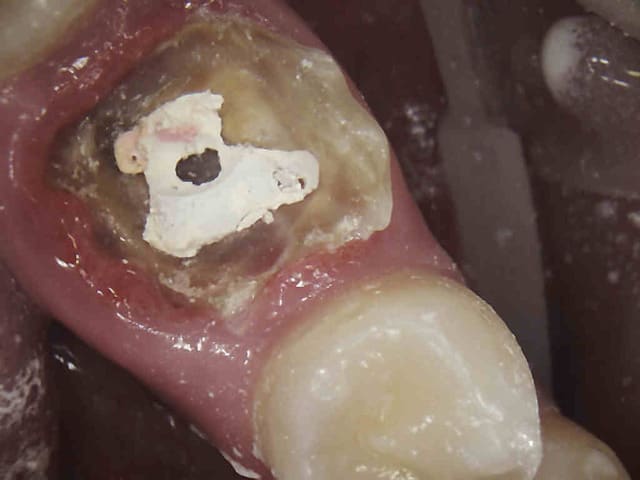

Par exemple : là j'en ai marre je vire 3 scew posts à déposer et RTE à 2 balles avec une pèche bien avancée, la merde.

Comment fait tu pour obtenir une éviction gingivale comme celle de tes photos